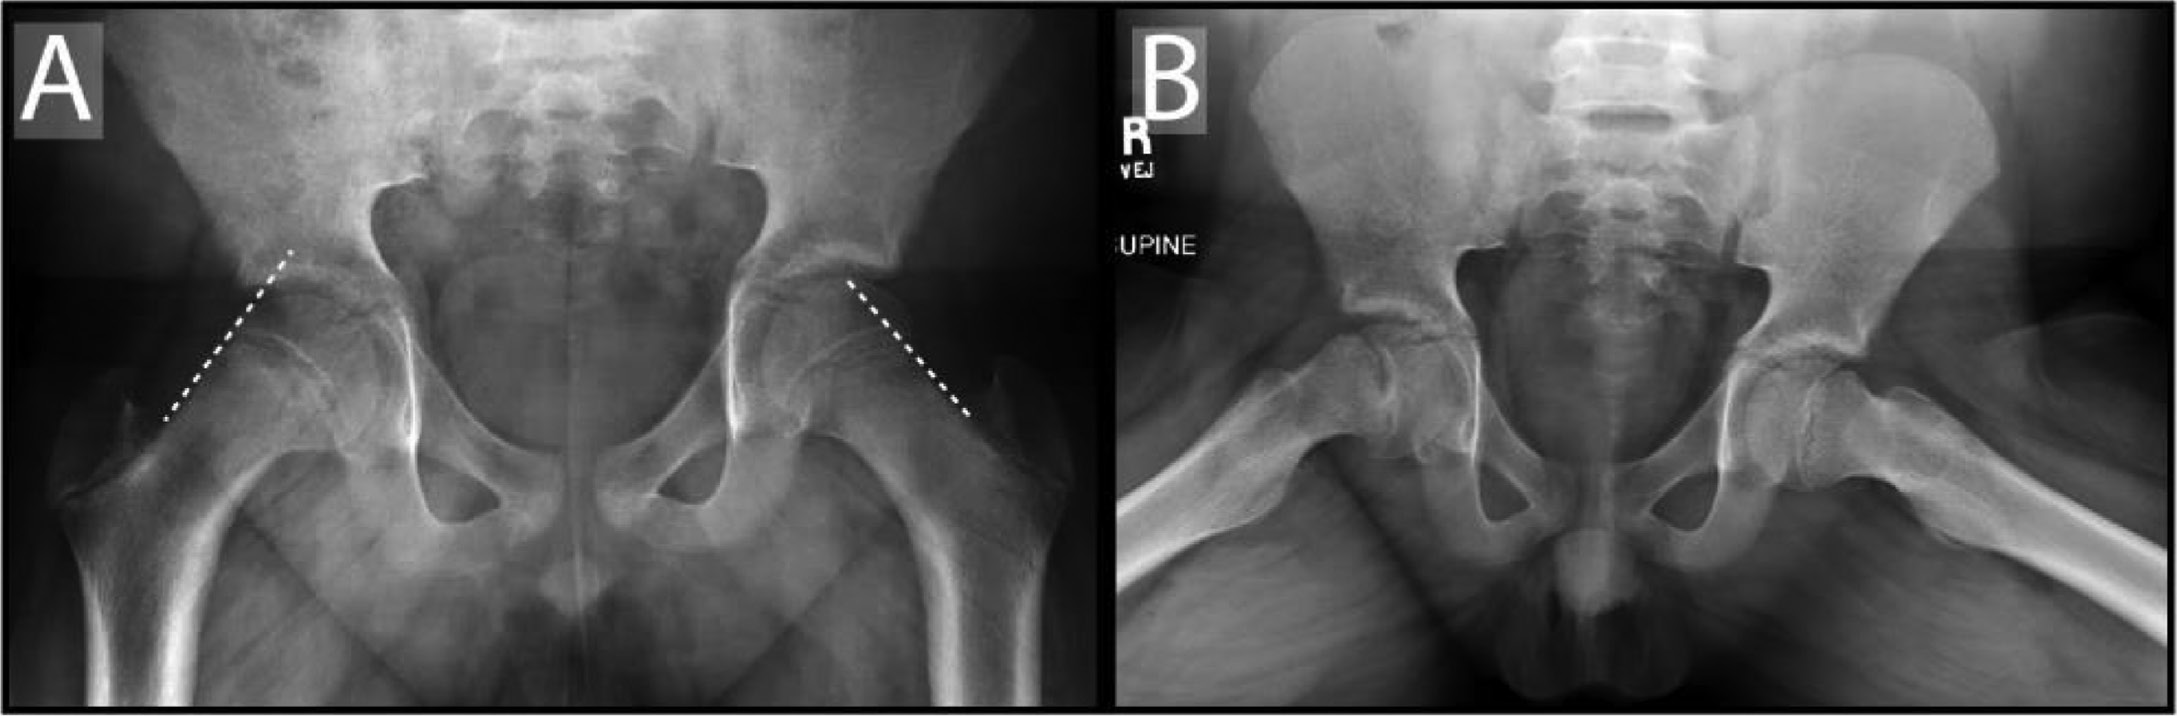

Maranho et al.71 modified this technique to measure the posterior epiphyseal tilt relative to the femoral neck (rather than the femoral shaft, Figure 6). They measured epiphyseal tilt angle in 318 hips at presentation of unilateral SCFE and determined that for each additional degree of posterior epiphyseal tilt, there was an 8% increase in likelihood of contralateral slip. Hips with posterior tilt angle of <10 degrees had only a 19% chance of contralateral slip while hips with >10 degrees had a 49% chance of a contralateral slip where the NNT for patients with a tilt angle >10 degrees was 3.3.

Figure 6. Posterior epiphyseal tilt is determined by first drawing a line perpendicular to the edges of the epiphysis on the frog lateral view (black line). The epiphyseal tilt (tilt angle) is then measured as the angle subtended by the line perpendicular to the epiphysis and a line parallel to the femoral neck axis (white line). In this case, the epiphysis has a slight posterior epiphyseal tilt.